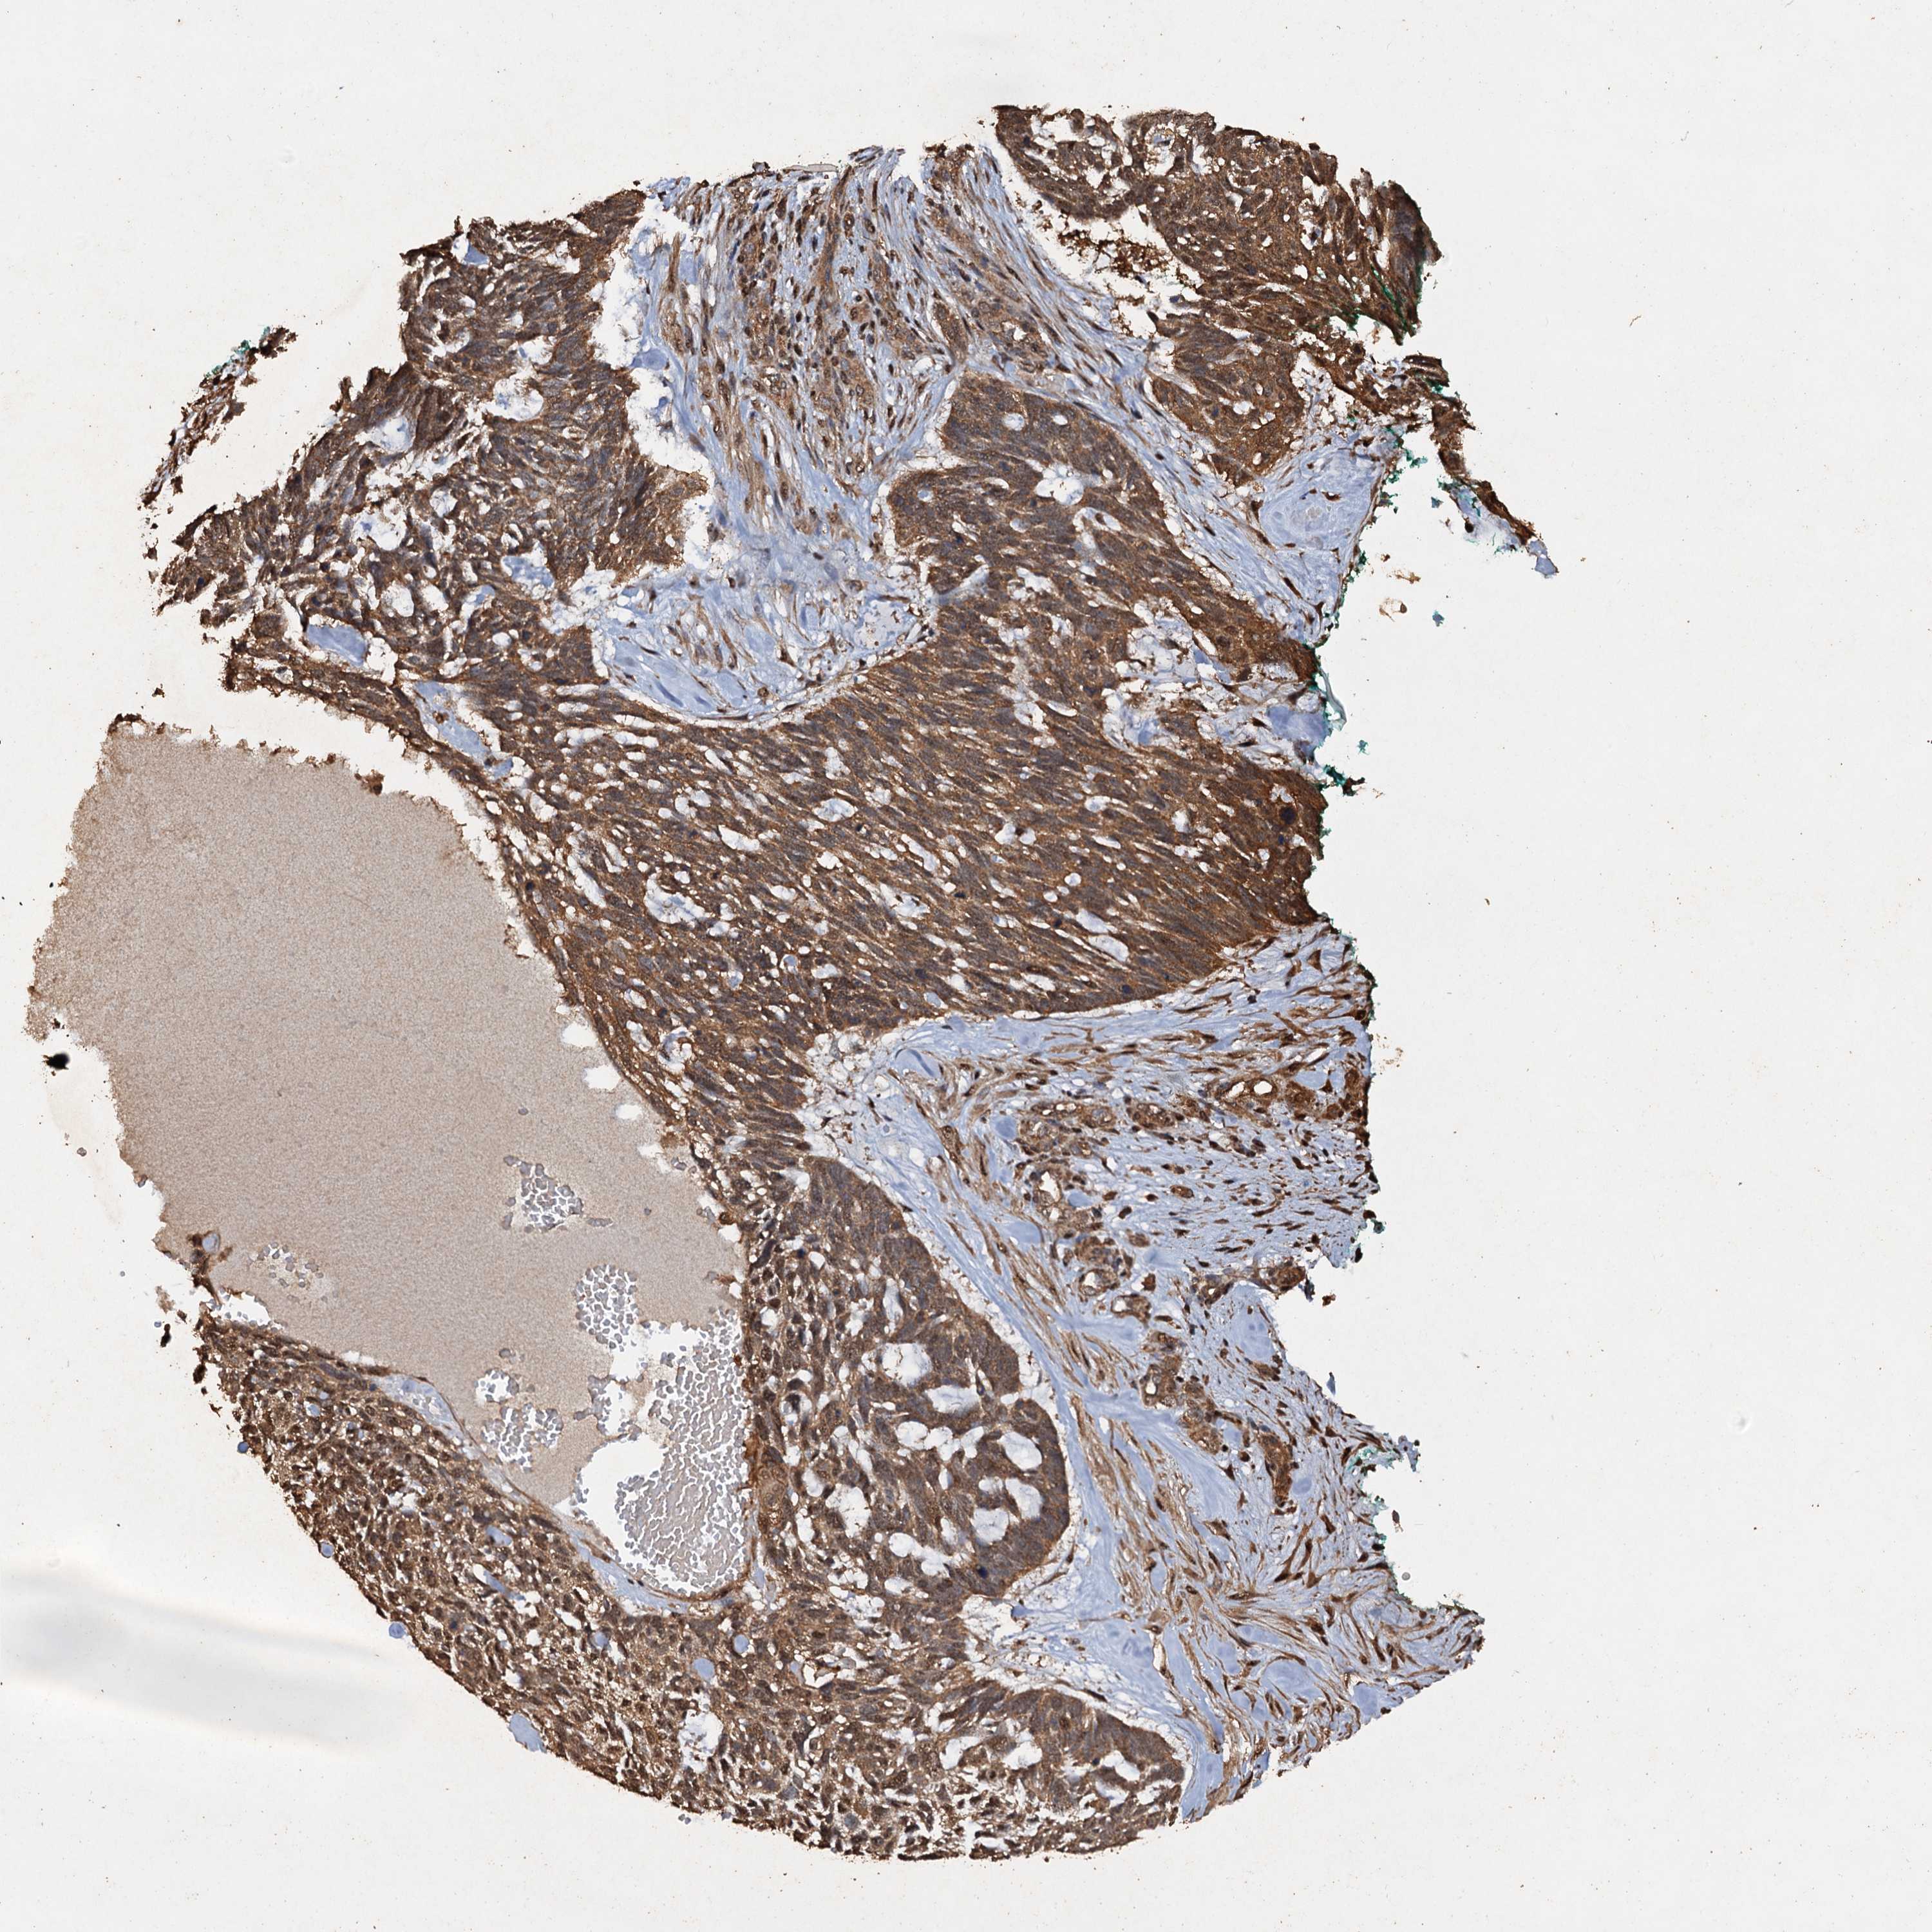

CANCER SKIN CANCER Show tissue menu

Basal cell and squamous cell cancer

SKIN CANCER - Protein expressioni

A mouse-over function shows sample information and annotation data. Click on an image to view it in a full screen mode. Samples can be filtered based on level of antibody staining by selecting one or several of the following categories: high, medium, low and not detected. The assay and annotation is described here.

Each image is clickable and will lead to virtual microscopy that enables deeper exploration of all samples and also displays staining intensity scores, fraction scores and subcellular localization as well as patient and tissue information for each sample.

Antibody HPA040512

Basal cell carcinoma